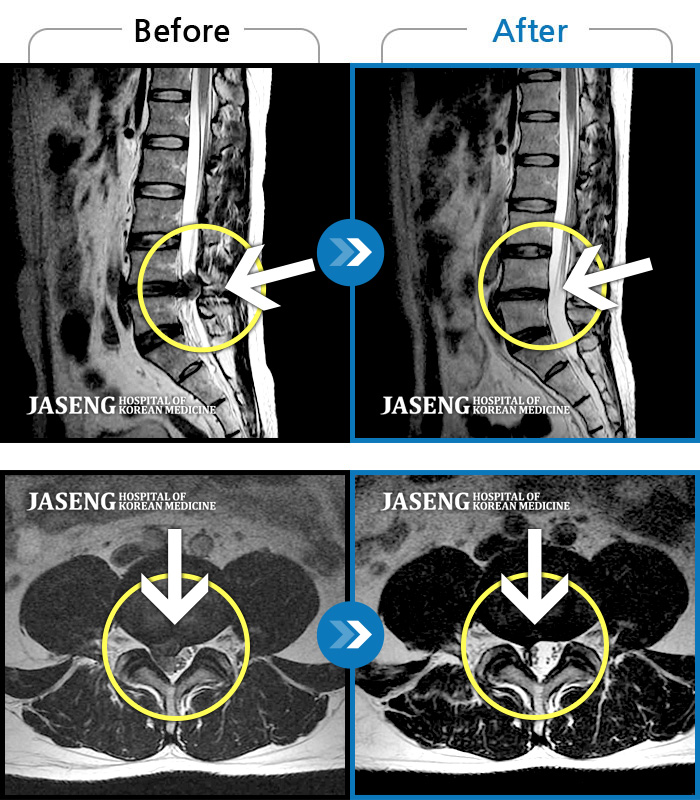

MRI 치료사례

우측 다리가 발끝까지 저려요.